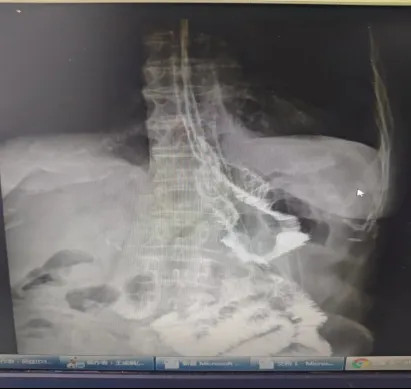

67岁吴依姆因患有尿毒症,已经持续血透4年了,近一个月以来逐渐进食困难,身体每况愈下。经过当地医院胃镜检查,发现胃底贲门位有巨大溃疡型肿物,病理结果证实为——“贲门下”神经内分泌癌(小细胞),且病情已发展到相当严重的阶段。术前CT影像显示,肿瘤侵袭范围广泛,贲门至胃底部壁增厚,考虑MT并小弯侧多发淋巴结肿大,肿瘤已阻塞了胃贲门(胃入口),这才使得吴依姆陷入无法正常进食的状况。

术前CT图像